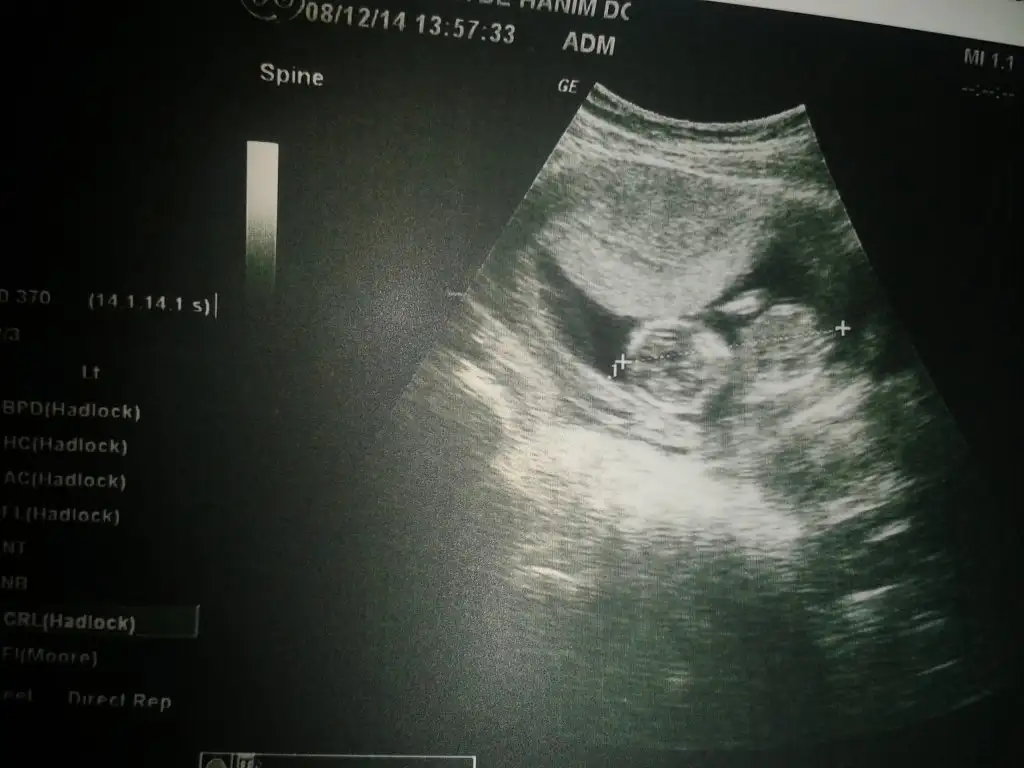

Merhabalar,daha oncedende koymustum,doktorum bilemedi meraktayim..))) 14+5 gunluk bebisim

Lutfen yorum yaparmisiniz,tesekkurler

ecan77, post: 38331411, member: 315712"]Merhabalar,daha oncedende koymustum,doktorum bilemedi meraktayim..))) 14+5 gunluk bebisim

Lutfen yorum yaparmisiniz,tesekkurler[/QUOTE]